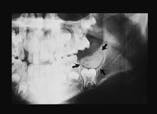

Case 10

Complex odontoma

2. Identify the radiographic appearance of the complex odontoma.

a. multilocular radiolucency

b. unilocular radiolucency

c. radiopacity with radiolucent rim

d. radiolucency with radiopaque flecks

e. none of the above